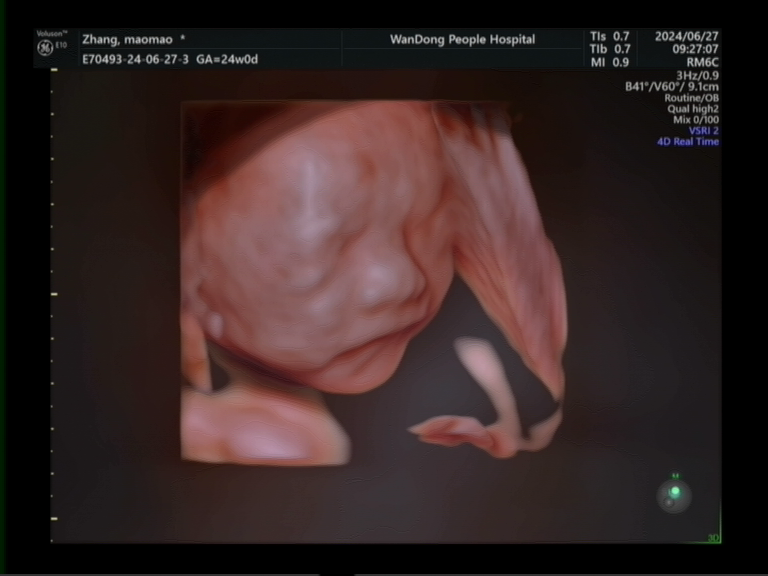

超聲科目前擁有多臺國內(nèi)、國際先進(jìn)的高檔彩色超聲診斷儀:GE-E10四維彩超、GE-E9、GE-S8、飛利浦iU22等,并配備床邊便攜式高檔超聲診斷儀飛利浦CX-50。儀器圖像清晰,分辨率高,各種專用探頭配備齊全,并采用超聲圖文工作站對報告及檔案實行信息化管理。

特色醫(yī)療:目前開展項目包括腹部、心臟、血管、婦產(chǎn)及淺表器官(甲狀腺、乳腺)、并開展腔內(nèi)彩超(經(jīng)陰道超聲檢查、經(jīng)直腸前列腺超聲檢查)等;近年來為了降低胎兒出生缺陷,提高生存質(zhì)量,提升診斷準(zhǔn)確性,開展了胎兒早孕期(NT)篩查、胎兒中孕期系統(tǒng)(四維)篩查、先天性小兒髖關(guān)節(jié)發(fā)育不良篩查、超聲引導(dǎo)下各臟器穿刺活檢等。同時我院為方便患者,開展了床旁超聲及24小時急診超聲服務(wù)。